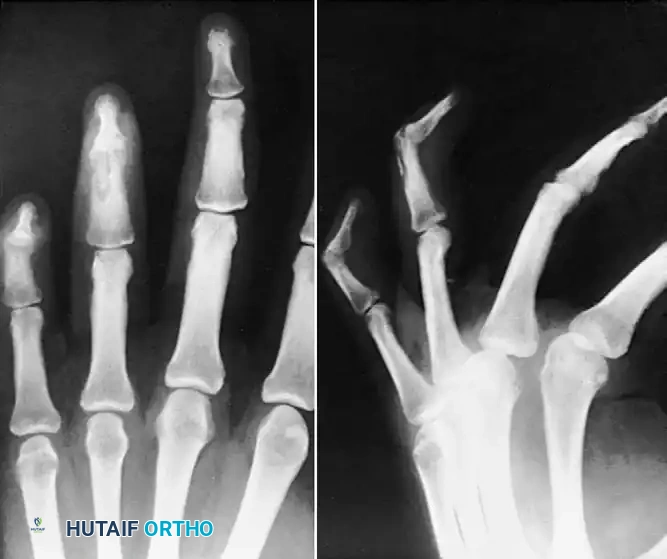

Osteitis and Osteomyelitis

If the infection breaches the subchondral bone, or if a contiguous soft tissue infection (such as a felon in the digital pulp) is left untreated, osteitis and subsequent osteomyelitis will develop.

FIGURE 78-16: Osteitis of the distal phalanx caused by an untreated infection in the finger pulp (felon). Note the lytic destruction and loss of cortical margins at the tuft.

As osteomyelitis progresses, the vascular supply to the bone is compromised by purulent exudate under pressure and septic microthrombi. This leads to ischemic necrosis of the bone, resulting in the formation of a sequestrum (a piece of dead bone that has become separated during the process of necrosis from normal bone).

FIGURE 78-17: Sequestrating osteomyelitis of the middle phalanx. The radiograph demonstrates profound bony destruction, periosteal reaction, and a central radiodense sequestrum surrounded by a radiolucent involucrum.